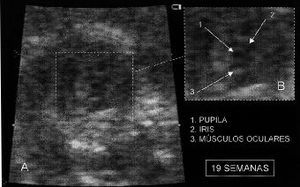

Para localizar la pupila se utilizaba el selector de ampliación regional («RES») del sistema de ultrasonidos. Mediante éste se expandía el área correspondiente a la cámara anterior ocular en una proyección frontal (Fig. 1). La imagen del iris se localizaba entre la inserción de los músculos oculares. Mediante un tenue movimiento de la sonda aparecía la imagen pupilar que se mostraba por las imágenes memorizadas en el ecógrafo (Figs. 2 y 3). El fotograma correcto era digitalizado a través de una tarjeta Targa plus (Truevision) para su archivo informático y ulterior análisis. En una fase posterior se realizaban las mediciones sobre las imágenes digitalizadas. El software de análisis de imagen utilizado fue el Image Tool for Windows v1.27 de Uthscsa (University of Texas Health Science Center in San Antonio)(4), calibrando el software en cada fotograma según la regla de graduación lateral de la imagen digitalizada del ecógrafo. Se midieron los perímetros de la pupila (PP) y del iris (PI). También se analizó la relación (PP/PI x 100) como verdadero índice del tamaño pupilar según la evolución del perímetro del iris. En el análisis estadístico se utilizó el software SPSS v6.0.1. El supuesto de normalidad se comprobó con el test de Shapiro-Wilks. Para el análisis estadístico de la relación (PP/PI x 100) se aplicó el test no paramétrico de Kruskal-Wallis, al no cumplirse el requisito de homogeneidad de varianzas.

Figura 1. Fotograma de la izquierda: colocación del selector de expansión regional sobre el ojo fetal, cámara anterior. En el esquema que aparece a la derecha se representa dónde se localiza el iris y la pupila: entre los músculos oculares y cámara anterior del ojo.

Figura 2. Fotograma A: Imagen en un feto en la semana 19. Fotograma B: Ampliación de la imagen señalando la pupila, iris y músculos oculares.